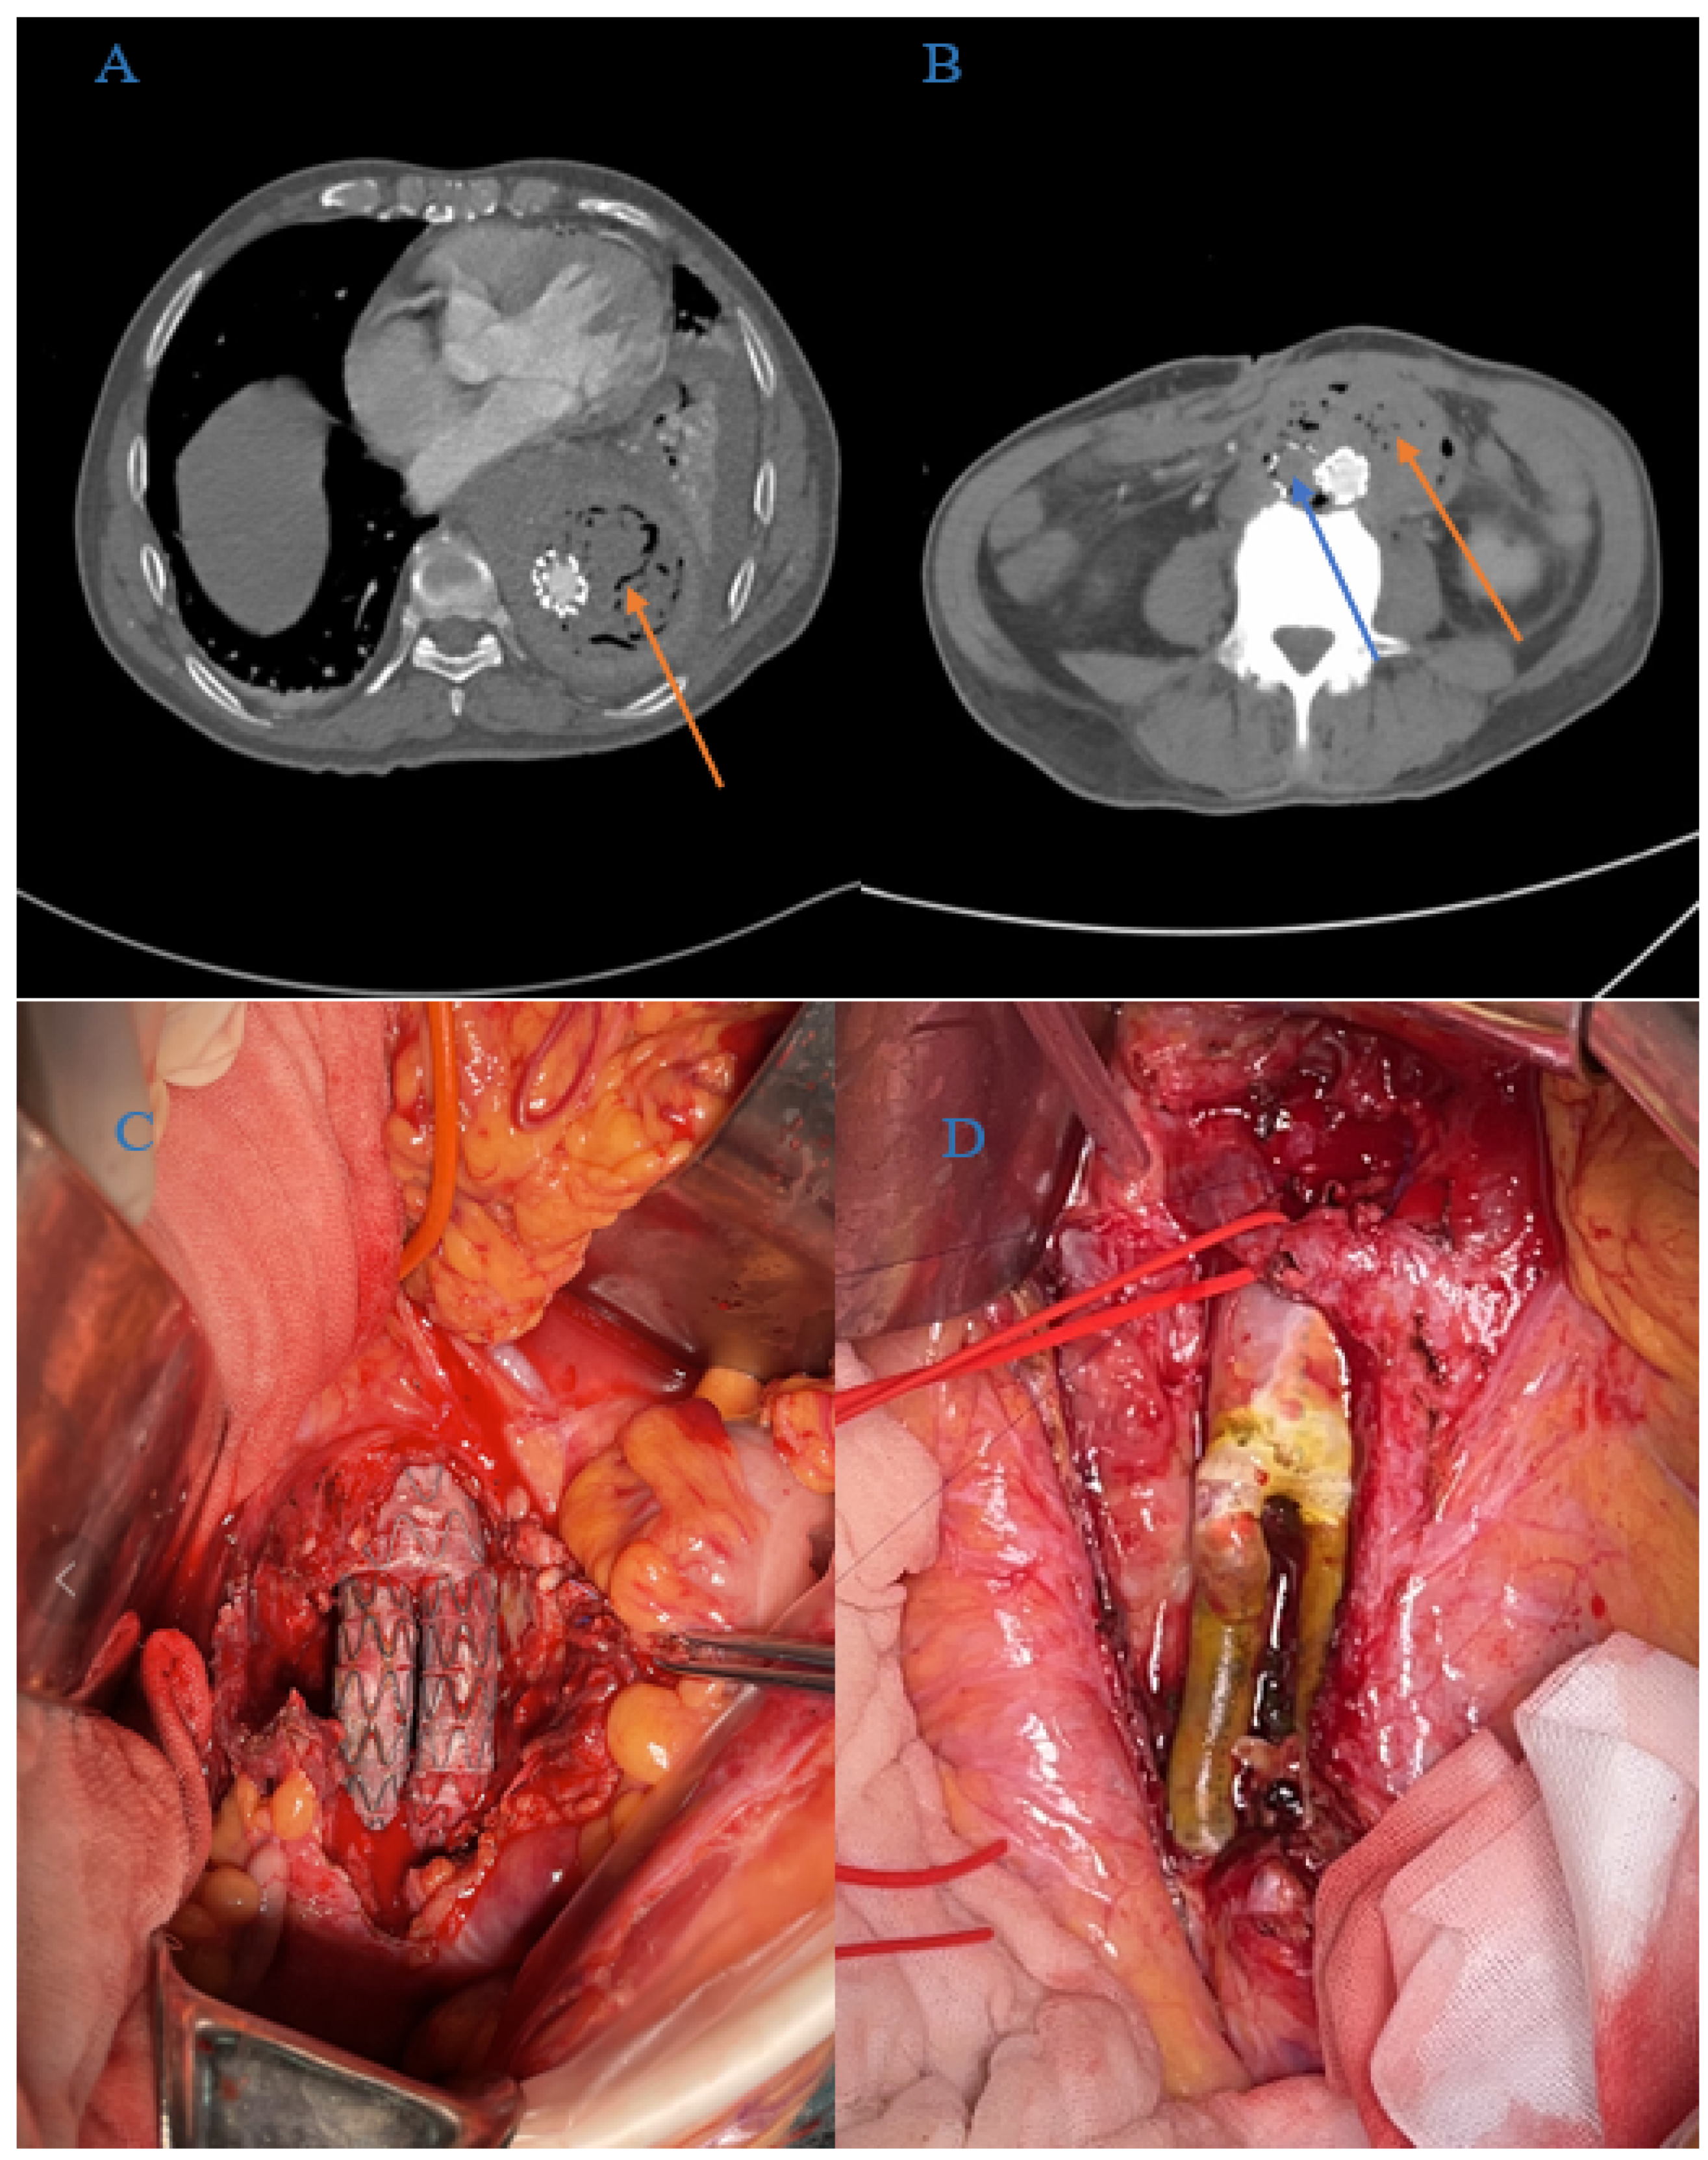

| Peri-graft/retroperitoneal abscess | 21 (48%) |

| Graft duodenal fistula | 10 (23%) |